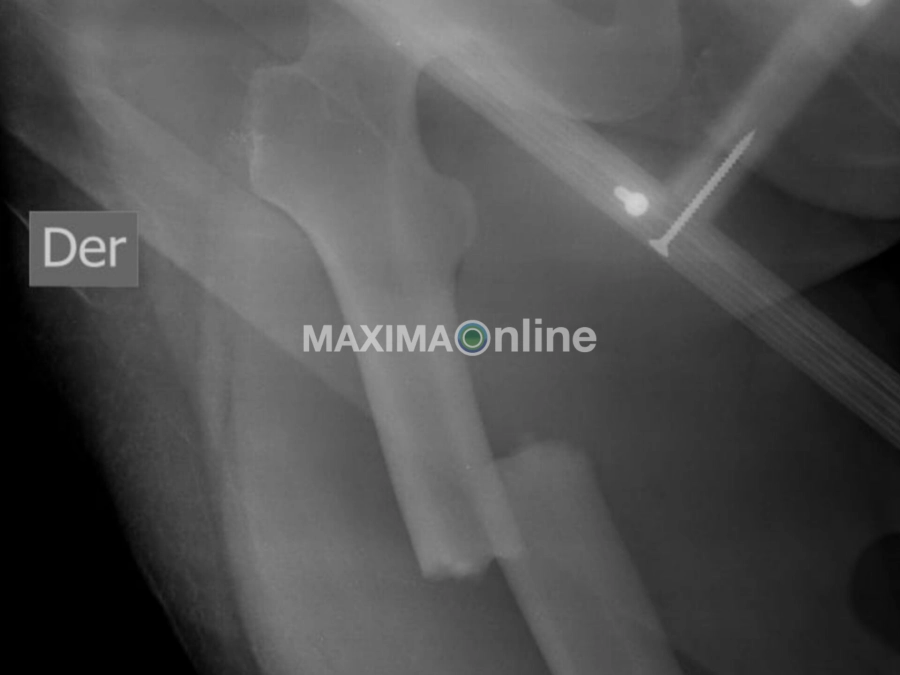

En la tragedia, Christian Claus, que conducía uno de los vehículos, sufrió fractura de fémur “y tiene la muñeca izquierda prácticamente desarmada, tiene un clavo en la pierna y dos placas en la muñeca con tornillo”, según relató su hermana Andrea.